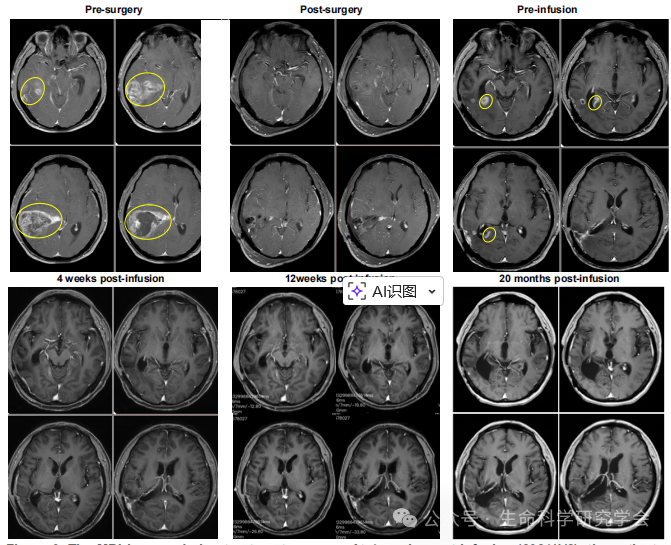

患者为 56 岁男性,左额叶 GBM(IDH 野生型、EGFR 扩增)。在经历放化疗 + CAR-T(累计 17 次,靶向 IL-13Rα2 与 B7-H3)仍进展后,于 2023年11月 入组 TIL 临床试验。 2023/12/12:TIL 输注(GC101) 基线 MRI:复发病灶最大径 2.8 cm 4 周后(2024/1/8):MRI 显示病灶完全消失 随访至 2025/10:持续完全缓解(CR),无新发灶 治疗前、4 周后、20 月后的对比 更令人关注的是: 这说明 TIL 不仅成功跨越血脑屏障,还在颅内形成了持久免疫监视。 04|“冷肿瘤”被点燃:科学意义与未来前景